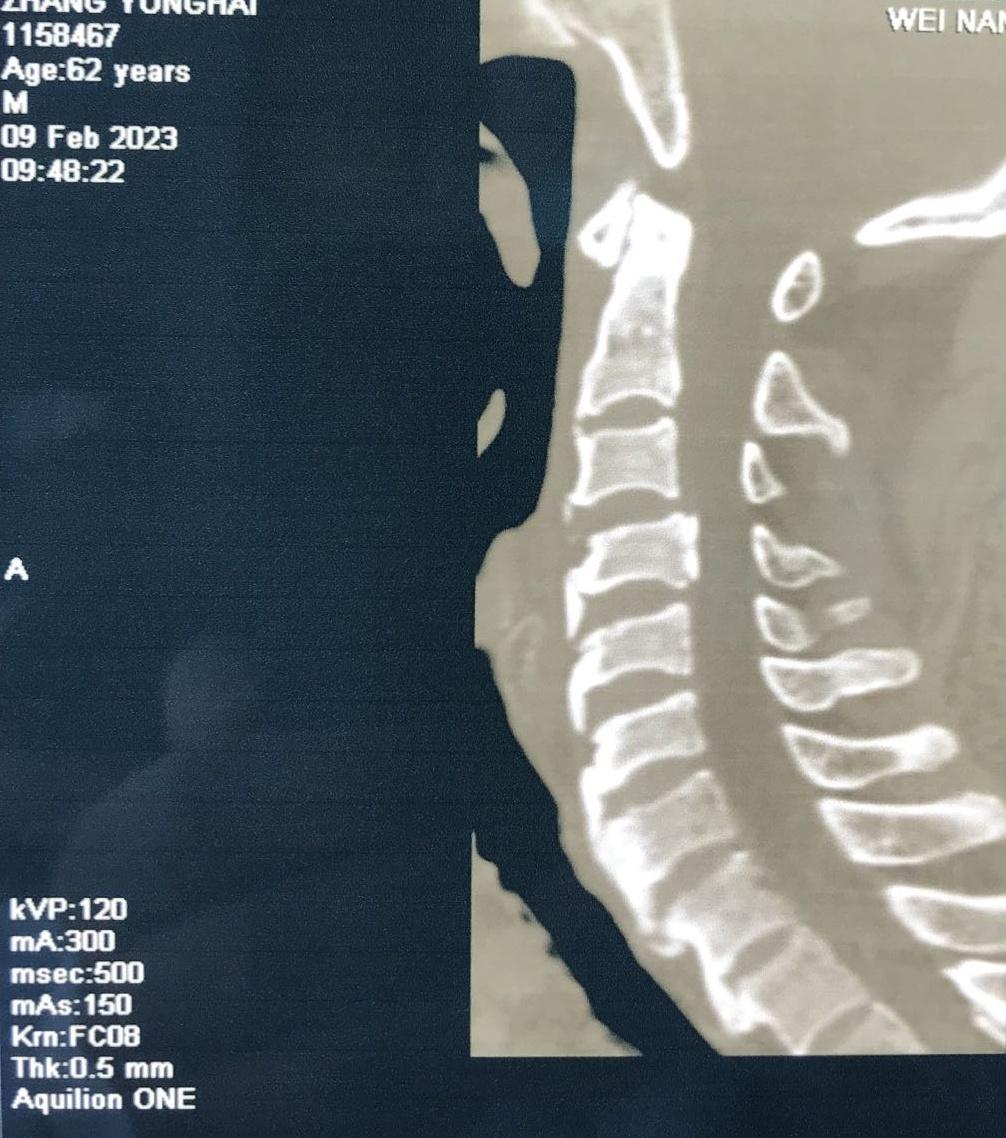

近日,一位颈部外伤合并肢体瘫痪症状患者来到MILAN.COM骨一科就诊。经入院后紧急检查,发现患者为颈3.4椎体骨折、脱位,并有右后侧关节突关节骨折、绞索,四肢肌力约3级。

入院后,科室立即进行常规术前检查,给予8公斤大重量颈枕带牵引,但因关节脱位的绞索,颈椎复位困难。几日后,患者在牵引过程中出现右上肢抽痛加重,肌力减低表现。紧急时刻,骨一科决定立即为患者行急诊手术治疗。

经过有序准备,为患者先行颈后路减压,解锁关节突绞索,牵引复位,使用颈椎侧块螺钉固定,同时椎板间植骨融合。随后再将患者转为仰卧位,再行颈前路脱位椎体的间盘摘除,融合器植入,钢板螺钉固定,历时3小时,顺利结束。患者术后恢复良好,肢体功能状态较术前改善显著,上肢抽痛症状消失,肌力已达4-5级,患者及家属对治疗效果颇为满意。